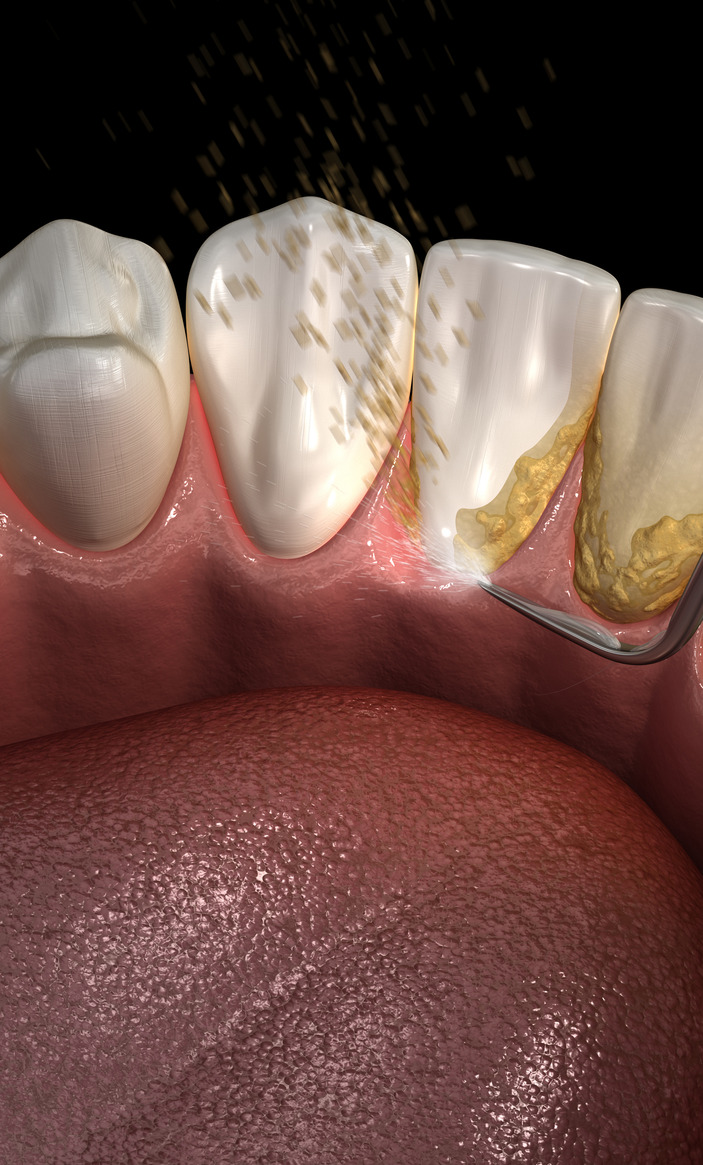

Regular teeth cleaning is one of the most important steps you can take to maintain a healthy mouth. Even with excellent brushing and flossing habits, plaque and tartar can build up in hard-to-reach areas, leading to gum inflammation, bad breath, cavities, and gum disease. Professional cleanings help prevent these issues and keep your teeth and gums healthy for life.

A dental cleaning—also called prophylaxis—is a preventive procedure performed by your dentist or dental hygienist to remove plaque, tartar, and stains from your teeth.

Daily brushing and flossing remove most plaque, but once plaque hardens into tartar (calculus), only a dental professional can remove it. Cleanings protect the gums, prevent cavities, reduce inflammation, and keep your smile bright and fresh.

Left untreated, buildup around the teeth can lead to gum infection, bone loss, loose teeth, and eventually tooth loss. Regular cleanings help reverse early inflammation, stop disease progression, and maintain long-term health.

- Plaque forms daily where the gumline meets the tooth.

- If not removed, it hardens into tartar, which cannot be brushed off.

- Tartar irritates the gums, causing gingivitis (early gum disease).

- Scaling:

Removal of plaque and tartar from above and below the gumline using hand instruments or an ultrasonic scaler. - Polishing: